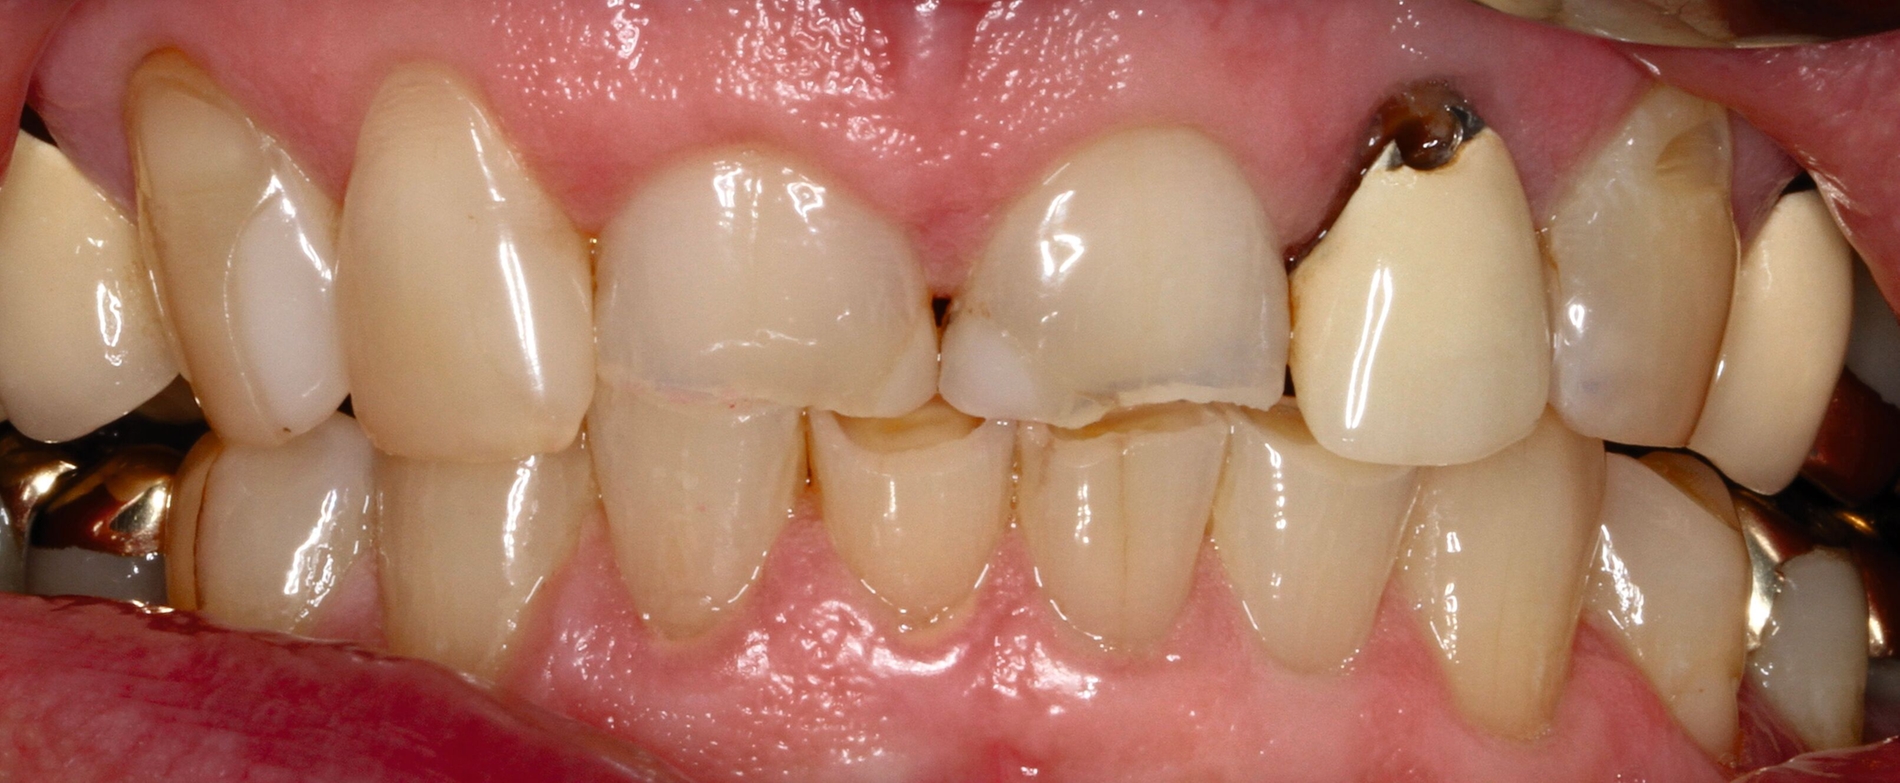

Die dentale Ausgangssituation zeigte im Seitenzahnbereich ein suffizient konservierend und prothetisch versorgtes Gebiss der zweiten Dentition sowie im Frontzahnbereich nicht kariogene Zahnhartsubstanzverluste und eine defekte Krone mit Sekundärkaries (Abbildungen 1 und 2).

Zur Verbesserung der Ästhetik und des Wohlbefindens des Patienten standen die Harmonisierung der Lachlinie und des Frontzahnbogens sowie Farb- und Formkorrekturen der Oberkieferfrontzähne im Fokus. An den Zähnen 11 und 21 waren Zahnhartsubstanzverluste durch Erosion und Attrition zu erkennen. Zahn 23 hatte ebenfalls einen erosiven Defekt, Zahn 13 eine farblich abweichende Kompositrestauration und die Zähne 14 und 24 wiesen keilförmige Defekte zervikal der Kronenränder auf, die einen suffizienten Randschluss haben (Abbildung 1a).

Die Zähne 11, 21 und 32–42 wiesen aufgrund des Zahnverschleißes stark verkürzte klinische Kronen auf. Durch diese Zahnhartsubstanzverluste sind die genannten Zähne über die Zeit elongiert – gut erkennbar an dem in Richtung Okklusionsebene verschobenen Verlauf des Gingivalsaums –, wodurch sich ein frontaler Tiefbiss und in Protrusion eine verzahnte Frontzahnführung im Schlüssel-Schloss-Prinzip mit veränderter Rot-Weiß-Ästhetik adaptiert haben. Daraus resultiert ein verringertes Platzangebot in statischer und in dynamischer Okklusion (Abbildungen 1b und 1d).